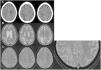

ResultsIn all three cases MRI showed the cortical hypointensity adjacent to the white-matter lesion in the T2-weighted gradient-echo sequence. In the patient with multiple sclerosis, this sign appeared earlier than the abnormal signal in the white matter. The patient being treated with rituximab was diagnosed postmortem and the pathology findings correlated with the MRI findings.

ResultadosEn los tres casos se observa en la RM el hallazgo de hipointensidad cortical adyacente a la lesión de la sustancia blanca en la secuencia EGT2. En la paciente con esclerosis múltiple, este signo fue más precoz que la alteración de señal en la sustancia blanca. El paciente en tratamiento con rituximab fue diagnosticado post mortem y se presenta una correlación radiopatológica.